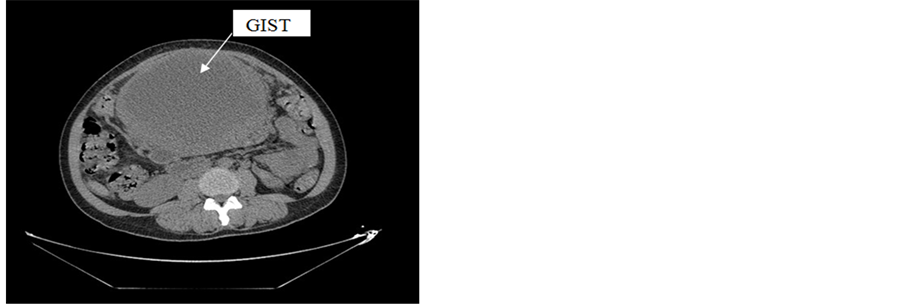

Post operative abdominal CT had objectified a large epigastric mass measuring 16 × 21 × 23 cm in diameter, limited and bilobed with dual components: fleshy peripheral component enhanced after contrast and liquefied central component with significant vasculature. This tumor mass increased comparing to the results of the MRI (Figure 3).

Figure 3. Axial view of the stromal tumor in abdominal CT.